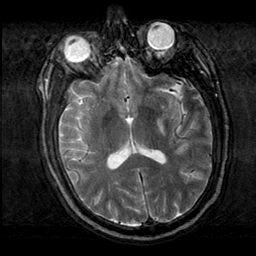

Subacute Stroke, overlay -- Slice #13

[Home][Help][Clinical] Slice 13